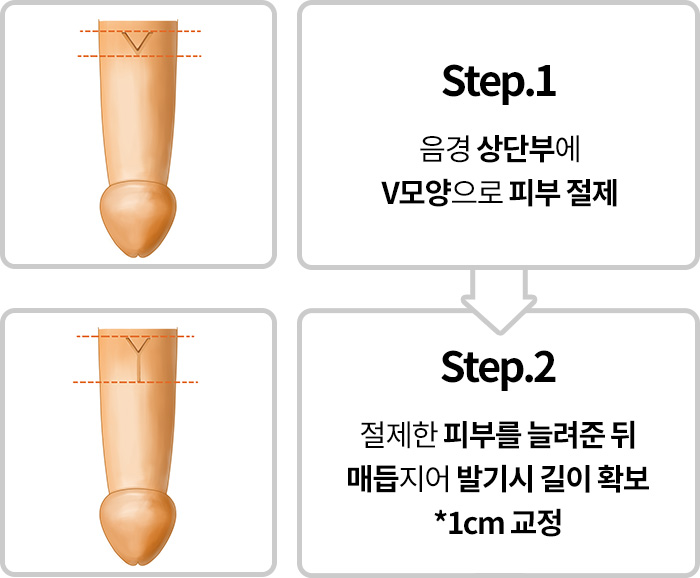

수술방법

이식재 삽입, 백막고정을 통한 무게추 및

지지효과로 성기 매몰증상 억제

*확대수술을 통해 2~4cm 길이연장 가능